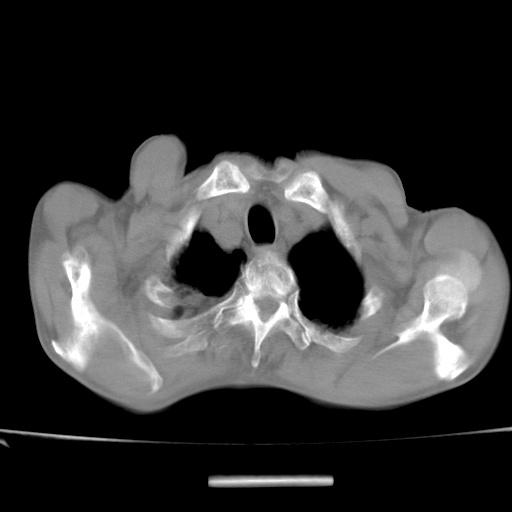

标题: CT13796:请会诊右上费病变!

患者男80岁,反复咳嗽多年,咳喘伴咯血1月

右上肺周围型肺癌伴肺门淋巴结转移.右上肺继发型肺结核.

右上肺周围型肺癌伴肺门淋巴结转移

右肺上叶占位性病变,考虑周围型肺癌,肺门淋巴结转移。要是能提供更多的临床资料就好了,以供鉴别诊断。

右肺尖周围型肺癌伴肺门淋巴结肿大

右肺上叶占位性病变,考虑周围型肺癌,肺门淋巴结转移。

右上肺周围型肺癌伴肺门、纵膈淋巴结转移

考虑为:右肺上叶肺癌伴阻塞性肺炎、右肺门及纵膈淋巴结转移。